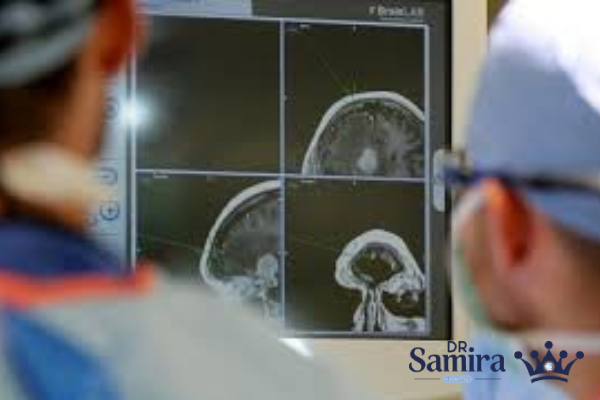

اپاندیموم گرید ۳ یا همان اپاندیموم آناپلاستیک یکی از تومورهای بدخیم و تهاجمی دستگاه عصبی مرکزی است. این بیماری از سلولهای اپاندیمال منشأ میگیرد؛ سلولهایی که وظیفه آنها تولید و تنظیم مایع مغزی-نخاعی (CSF) در بطنهای مغزی و کانال نخاع است. آنچه این نوع تومور را خطرناک میکند، سرعت رشد بالا، تمایل به عود پس از درمان و توانایی نفوذ به بافتهای مجاور است. برخلاف گریدهای پایینتر، اپاندیموم گرید ۳ نیاز به مداخلات جدیتری مثل جراحی وسیع و پرتودرمانی دارد و در بسیاری از موارد چالشهای زیادی برای بیمار و تیم درمانی ایجاد میکند.

اپاندیمومها به سه گرید تقسیم میشوند. گرید ۱ اغلب خوشخیم است، گرید ۲ رشد متوسط دارد و گرید ۳ یعنی همان آناپلاستیک، بدخیمترین شکل این تومور است. اپاندیموم گرید ۳ بیشتر در کودکان و نوجوانان دیده میشود، اما بزرگسالان هم میتوانند به آن مبتلا شوند. تفاوت اصلی این گرید با انواع دیگر در سرعت رشد، میزان تقسیم سلولی و احتمال عود پس از درمان است. به همین دلیل تشخیص به موقع و برنامهریزی دقیق درمانی اهمیت زیادی دارد.

وقتی نمونه تومور زیر میکروسکوپ بررسی میشود، دکتر سمیرا خالدی متوجه تفاوتهای بارز میان اپاندیموم گرید ۳ با انواع پایینتر میشوند. در این نوع، هستههای سلولی بزرگتر و نامنظم تر هستند، تعداد تقسیم سلولی به طور غیر عادی زیاد است و مناطقی از نکروز (مرگ سلولی) در بافت دیده میشود. این تغییرات نشاندهنده ماهیت تهاجمی تومور است و باعث میشود درمان آن پیچیدهتر و احتمال عود بیشتر باشد.

اولین و مهمترین اقدام درمانی، جراحی برای برداشتن تومور است. هر چه میزان برداشت تومور کاملتر باشد، احتمال عود کمتر و شانس بقا بیشتر خواهد بود. با این حال به دلیل قرارگیری تومور در نواحی حساس مثل ساقه مغز یا نخاع، همیشه امکان برداشت کامل وجود ندارد و جراح باید بین برداشتن تومور و جلوگیری از آسیب عصبی تعادل برقرار کند.

اپاندیموم گرید ۳ یک تومور بدخیم و تهاجمی سیستم عصبی مرکزی است که بیشتر در کودکان دیده میشود. این بیماری با علائمی مثل سردرد، استفراغ، تشنج و مشکلات حرکتی بروز میکند و تشخیص آن بر پایه MRI و بررسی بافتشناسی است. درمان شامل جراحی، پرتودرمانی و گاهی شیمیدرمانی است. با وجود اینکه پیشآگهی این بیماری همچنان چالشبرانگیز است، اما پیشرفتهای علمی نویدبخش درمانهای مؤثرتر و آیندهای امیدوارکننده برای بیماران و خانوادههای آنان است.